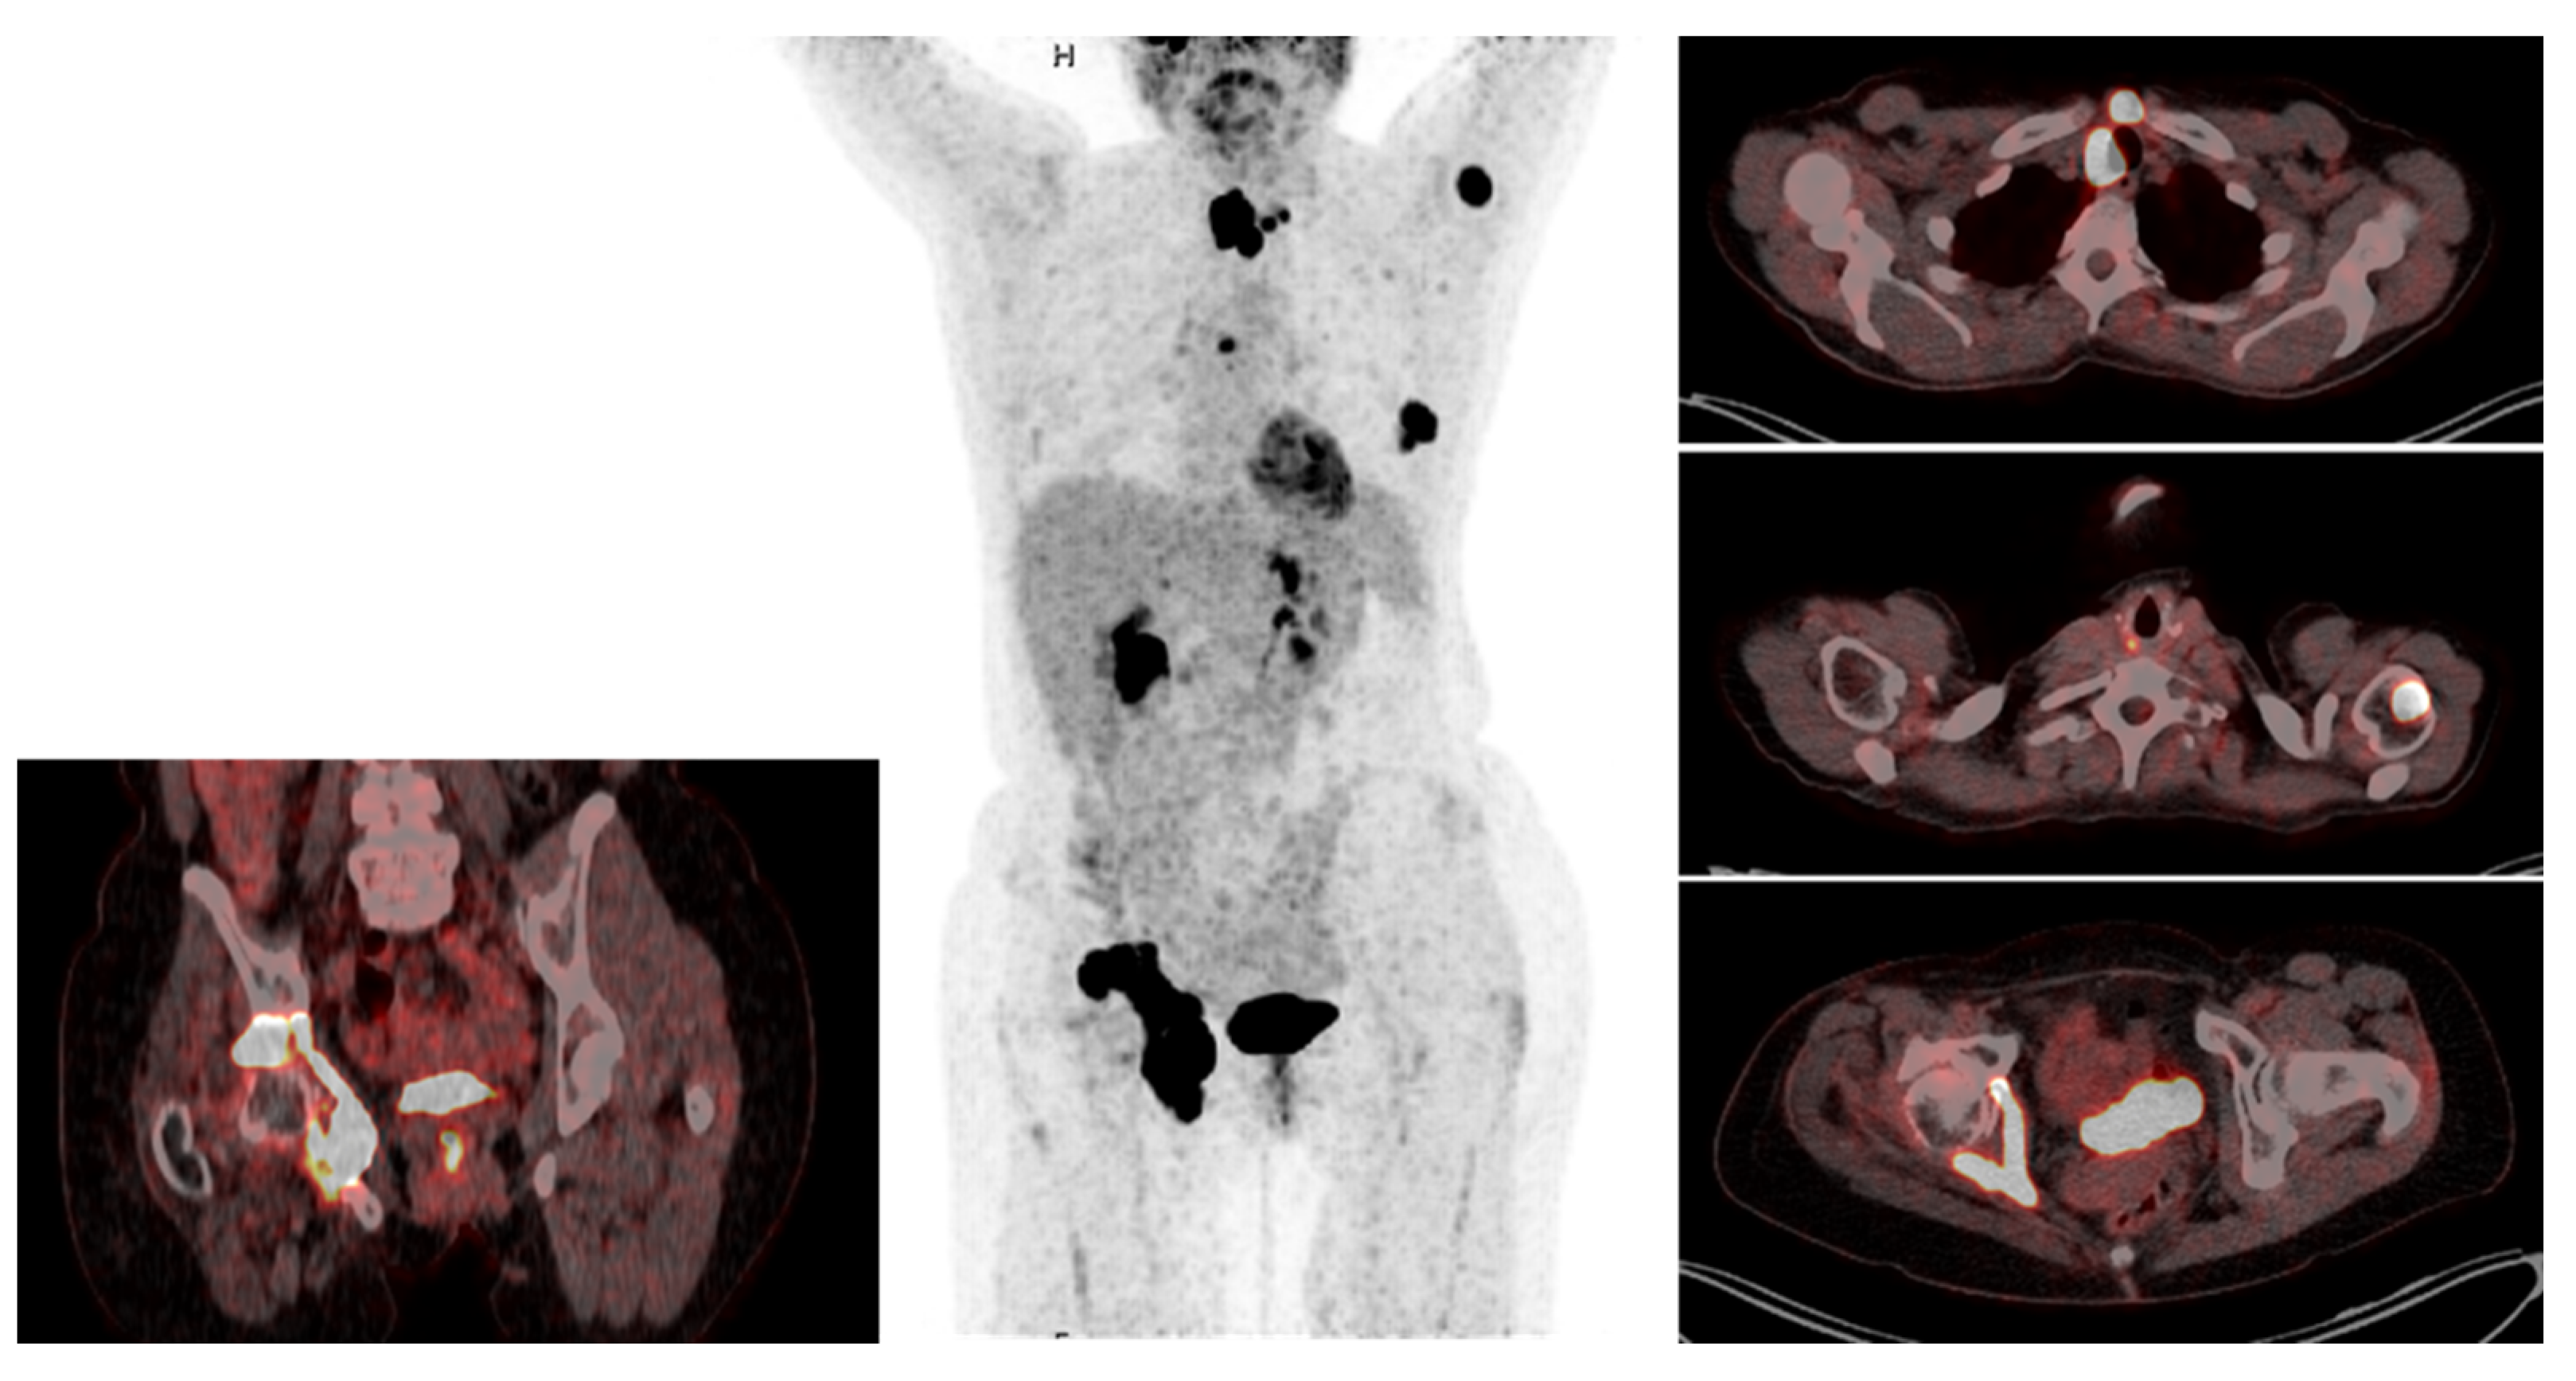

Surgery was generally indicated if DWBS was negative, but 18F-FDG PET-CT confirmed structural recurrence. Additionally, in case of radioiodine uptake but large tumor burden, pretherapeutic surgery was advocated in order to debulk tumor mass and reduce the burden to clear for radioiodine treatment or EBRT. Mostly surgical treatment consisted of cervical re-exploration and resection of the local recurrence. Indication to surgery was always initiated by the multidisciplinary endocrine team (MDET). In contrast to radioiodine refractory PTC [16], surgery for radioiodine refractory 18F-FDG-PET avid loco cervical recurrence of FTC was generally performed in patients displaying bone and/or other distant metastases (Figure 1).

Figure 1.

Cervical surgery in the setting of metastatic disease. This 55-year-old female patient underwent R0 resection of a minimally invasive pT3 cN0 cM0 FTC with vascular invasion 2014 and received her first RAIT. She first presented at our university clinic two years later, when she was diagnosed with cervical recurrence. She underwent cervical surgery, followed by cervical EBRT for diffuse soft tissue micrometastatic disease. Three years later, she was diagnosed with a new cervical relapse despite EBRT and a pelvic metastasis, which was deemed not resectable by orthopedic surgery. After her third cervical surgery in 2019, revealing soft tissue metastatic disease, she received a second RAIT and pelvic EBRT. These are the 18F-FDG PET scan and die DWBS six years after begin of disease. In addition to the pelvic metastasis and a further cervical relapse, new bone metastases are visible. The patient underwent her fourth cervical surgery this year. The trachea resulted superficially infiltrated over several cm, making a tracheal resection in the setting of metastatic disease not reasonable. A shaving resection was performed. Lenvatinib, which had been started 2020, was not tolerated well by the patient and treatment was discontinued. Disease is currently slowly progressing.